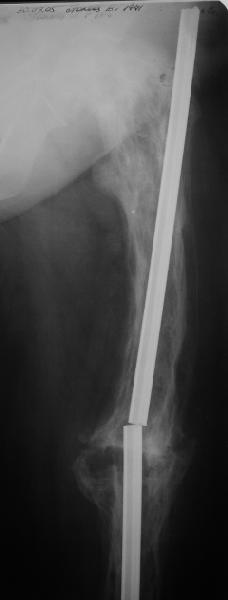

бывали ли у кого-нибудь такие случаи Уважаемые коллеги, вчера прооперировал женщину 60 лет с болезнью Педжета, переломом верхней трети бедра. Выявлена в августе этого года, сломала три дня назад от небольшого усилия. Из сопутствующих болезней лейкоз, сахарный диабет. Бывали ли кого-нибудь такие случаи, чем это все заканчивалось?

Пациент 82 лет, поступил через 5 мес. с несросшимся переломом после открытого интрамедуллярного остеосинтеза. Выполнили реостеосинтез стержнем 12 мм. ( мах. доступного нам в 2003 г.) Через 4 мес динамизация. В течении 2х лет сращения нет, тем не менее конечность опорна (ходит с тростью). От очередного реостеосинтеза отказались из-за сопутств. патологии.

Еще один пример. Пациентка с юга России, прислала рентгенограммы через год. На сегодня прошло 2 г. 8 мес. после операции. Несмотря на не очень убедительный процесс сращения, пациентка ходит. Учитывая остеопороз при Педжете, решили, что динамизировать вообще не нужно.

При переломах на фоне болезни Педжета металлоконструкция часто служит эндопротезом, несущим нагрузку. Динамизация индивидуальна,- по рентген-динамике. Основной упор- на медикаментозную терапию- см. канд. дисс. Колондаева А.Ф.

Стержень можно было бы поставить подлиннее.